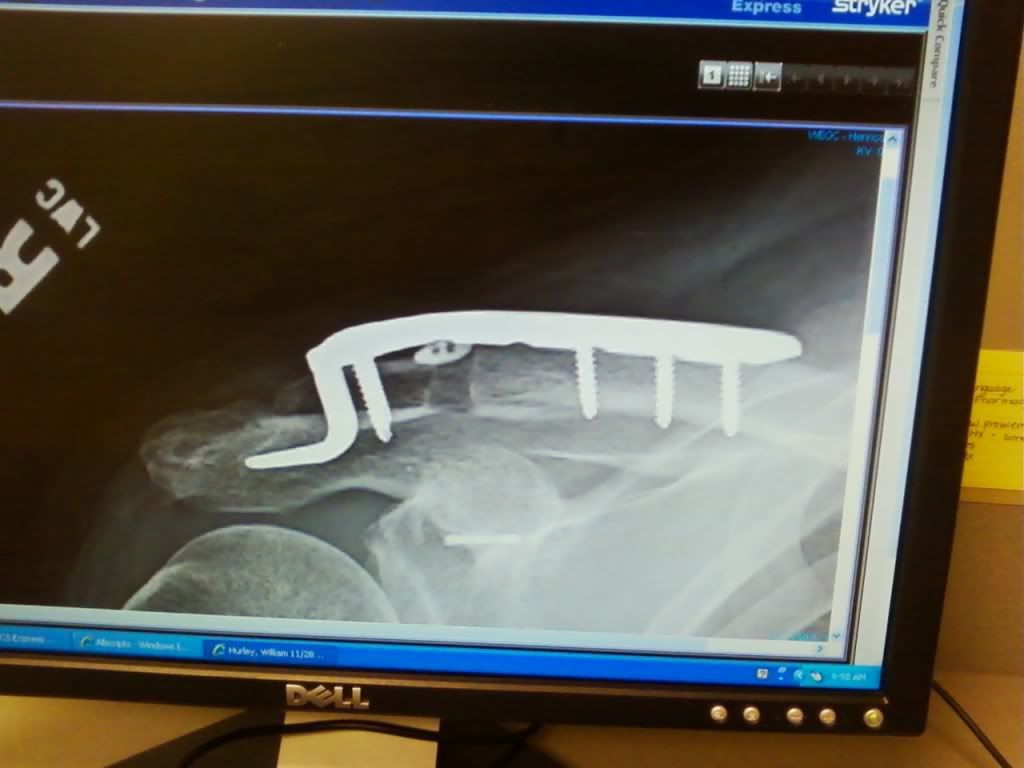

looks like you are becoming the bionic man, one piece at a time.....Nice to see you back.

Thank's everyone for the welcome back and the hope's for a speedy recovery. I am slowley getting there with the shoulder but therapy is killing me with a lot of pain in the range of motion department. I will suffer through it so that I can hunt.again this comeing deer season. I was not able to put a weapon up to my right shoulder at all this past season but did manage to get a doe and a nice 8 point with the left shoulder, one with the inline .50 cal. and one with my .270

Well believe it or not I am on the way this A.M. to Richmond to see about haveing my left Knee replaced. I was supposed to have it done last Jan. then I had the quad flip over on me on Christmas day and 3 shoulder surgerie's since then that put the knee on a back burner.